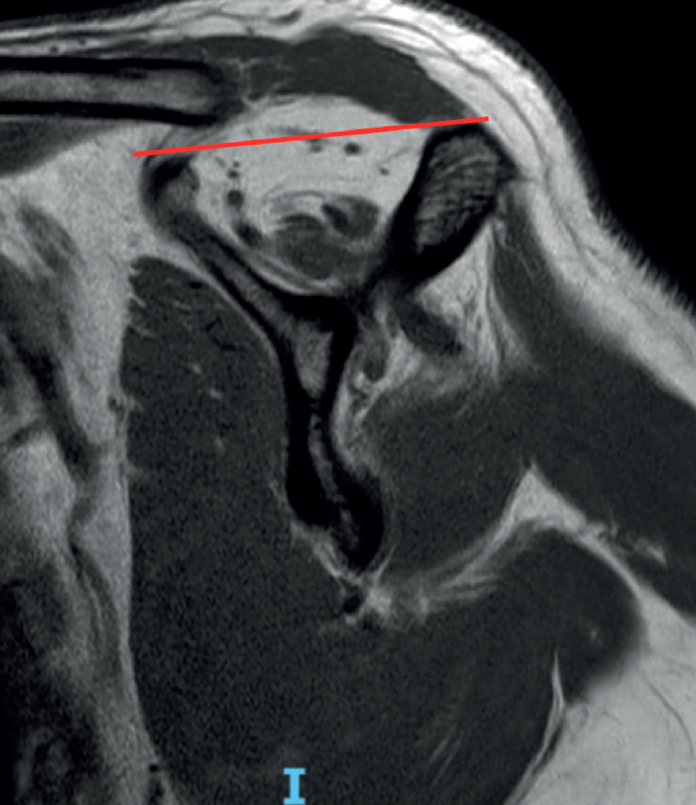

The fish backbone sign(18), in which the muscle belly presents a veined or streaky pattern reminiscent of a fish backbone, is another indicator of fatty infiltration of the muscle belly in the axial axis of the CAT scan, and is equivalent to Goutallier grade 3. The classification of Goutallier has been validated in MRI, and measurement is made in the sagittal section where the scapular spine comes into contact with the body of the scapula, producing a "Y" shaped image(19). Another predictor of irreparability and also an indicator of advanced fatty infiltration is the tangent sign of Zanetti et al.(20). According to the authors, advanced fatty infiltration is present when on tracing a line from the upper margin of the coracoid process to the upper margin of the scapular spine in the same sagittal section of an MRI scan in which a "Y" image is obtained, there is no cut in the muscle volume of the supraspinatus (Figure 3). When measuring in the sagittal view of an MRI scan, we must take into account that a healthy muscle presenting some retraction may simulate greater than real fatty infiltration, and conversely, the muscle may seem normal postoperatively, suggesting that the fatty infiltration has reverted, when in fact it is only healthy but retracted muscle. Fatty infiltration is irreversible and progressive, and although minor improvements have been observed after the repair of these tendons(21), the results are generally poorer than in situations of low grades of adipose atrophy, especially of the infraspinatus(22). Thus, one of the aims of early repair (within 2.5 years from symptoms onset) of rotator cuff injuries is to prevent the condition from progressing to higher grades of adipose atrophy associated with irreversible loss of function and the concept to irreparability(23).

Figure 3. Tangent sign of Zanetti with no cut in the volume of the supraspinatus in the parasagittal MRI view, where the coracoid process and scapular spine are identified.